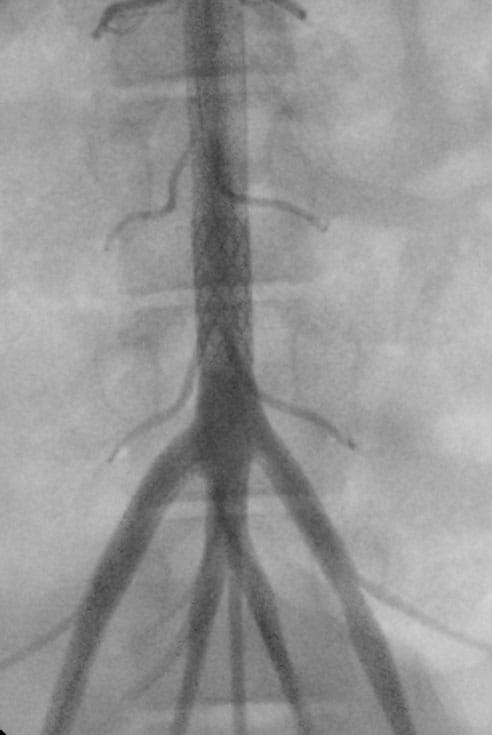

ZeBRAa Stent ZeBRa Stent implanted in the aorta in a preclinical model.

“The stents have excellent radial force, degrade in the desired amount of time and have a very low crossing profile, which means we can get them into our young patients despite their femoral arteries being quite small,” he says.